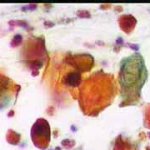

Papanicolaou: Πλακώδη επιθηλιακά κύτταρα κυρίως της επιφανειακήςστιβάδας, περίπου κατά50% και πλέον οξεόφιλα (16η ημέρα κύκλου!) . Ωστόσσο και αρκετά της διαμέσου και της παραβασικής, εν μέρει με διογκωμένους, ανισομεγέθειςαρραιοχρωματικούςδιαυγείςπυρήνεςKοιλοκυττάρωση.Η εικόνα συνηγορεί για δυσπλασία σοβαρού βαθμού.

Λόγω και του κολποσκοπικούευρήματος, μικροβιοψία που κατεδειξε ιστολογικώς CIN III